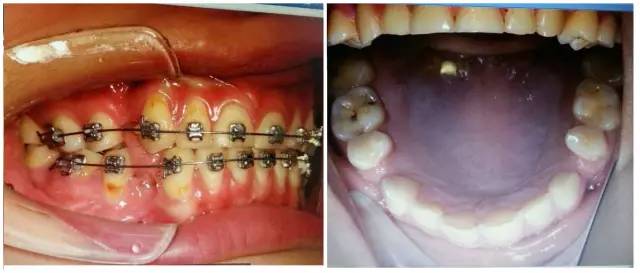

要想成為一個(gè)合格的(牙合)學(xué)醫(yī)生,僅僅局限于處理患者已經(jīng)出現(xiàn)的問(wèn)題是遠(yuǎn)遠(yuǎn)不夠的,善于挖掘患者潛在隱患的醫(yī)生才是合格的,細(xì)致入微的權(quán)老師還在病例中發(fā)現(xiàn)兩個(gè)潛在問(wèn)題,群里的同仁們,來(lái)吧,跟著權(quán)老師,看圖說(shuō)問(wèn)題。

7.jpg